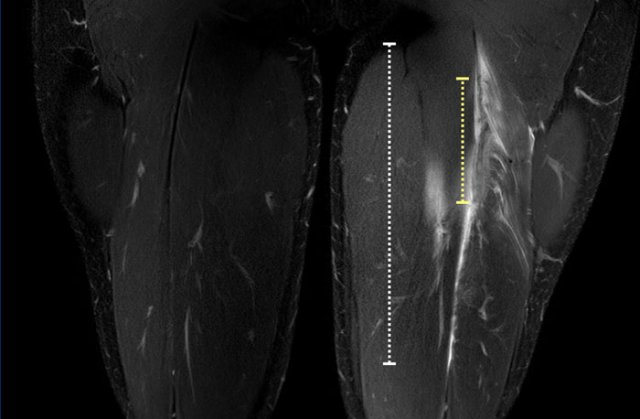

Total length of the edema is noted (white dotted line). Now take a closer look at the tendon (yellow dotted line) and continue reading.

Length of tendon distortion

When the tendon looks normal, straining is probable low grade.

Tendon thickening, tendon waviness, high signal of the tendon can all be signs of higher grade straining.

Case 1: normal tendon.

Case 2 slightly thickening and wavy aspect of a short length of the tendon.

Case 3: obvious thickening and waviness

All these signs have to be described in your report.

Total length of the distorted tendon is noted.

Both length of edema and distorted tendon are measured and noted in the report.

In this case, biceps femoris tendon injury was classified as grade 3 partial injury, since the length of the edema is > 15cm (white dotted line) and the length of the distorted tendon is > 5cm (yellow dotted line).

A muscle edema 5-10cm (white dotted line) present at the MTJ without architectural distortion of the tendon, classified as BAMIC 2b.

B muscle edema >15cm (white dotted line), at the MTJ / intramuscular tendon, tendon distortion > 5cm (yellow dotted line). The tendon shows disruption with loss of low signal intensity within the tendon along with a wavy appearance indicating focal loss of tension. BAMIC 3b/c.